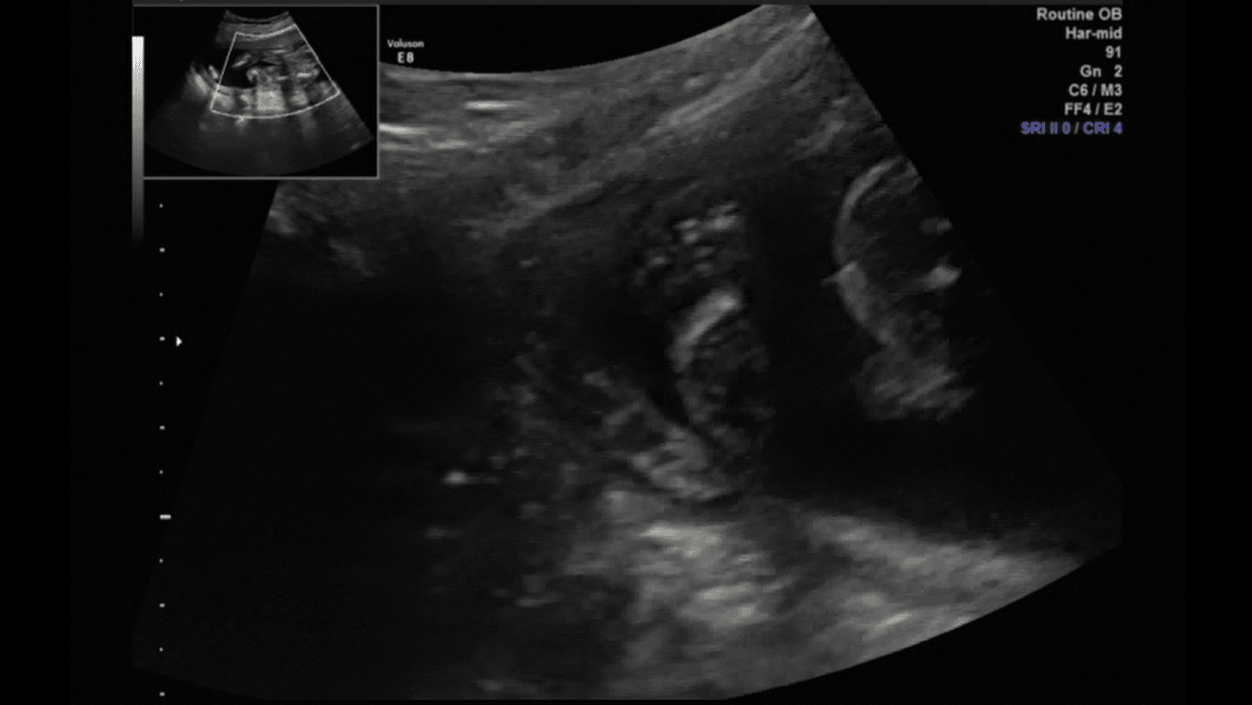

Porobiłam trochę screanów z usg połówkowego, więc pomyślałam, że wrzucę, mam nadzieję, że nie maci mi za złe ilości :D

Brzuszek, nóżki i klejnoty :D

2.png